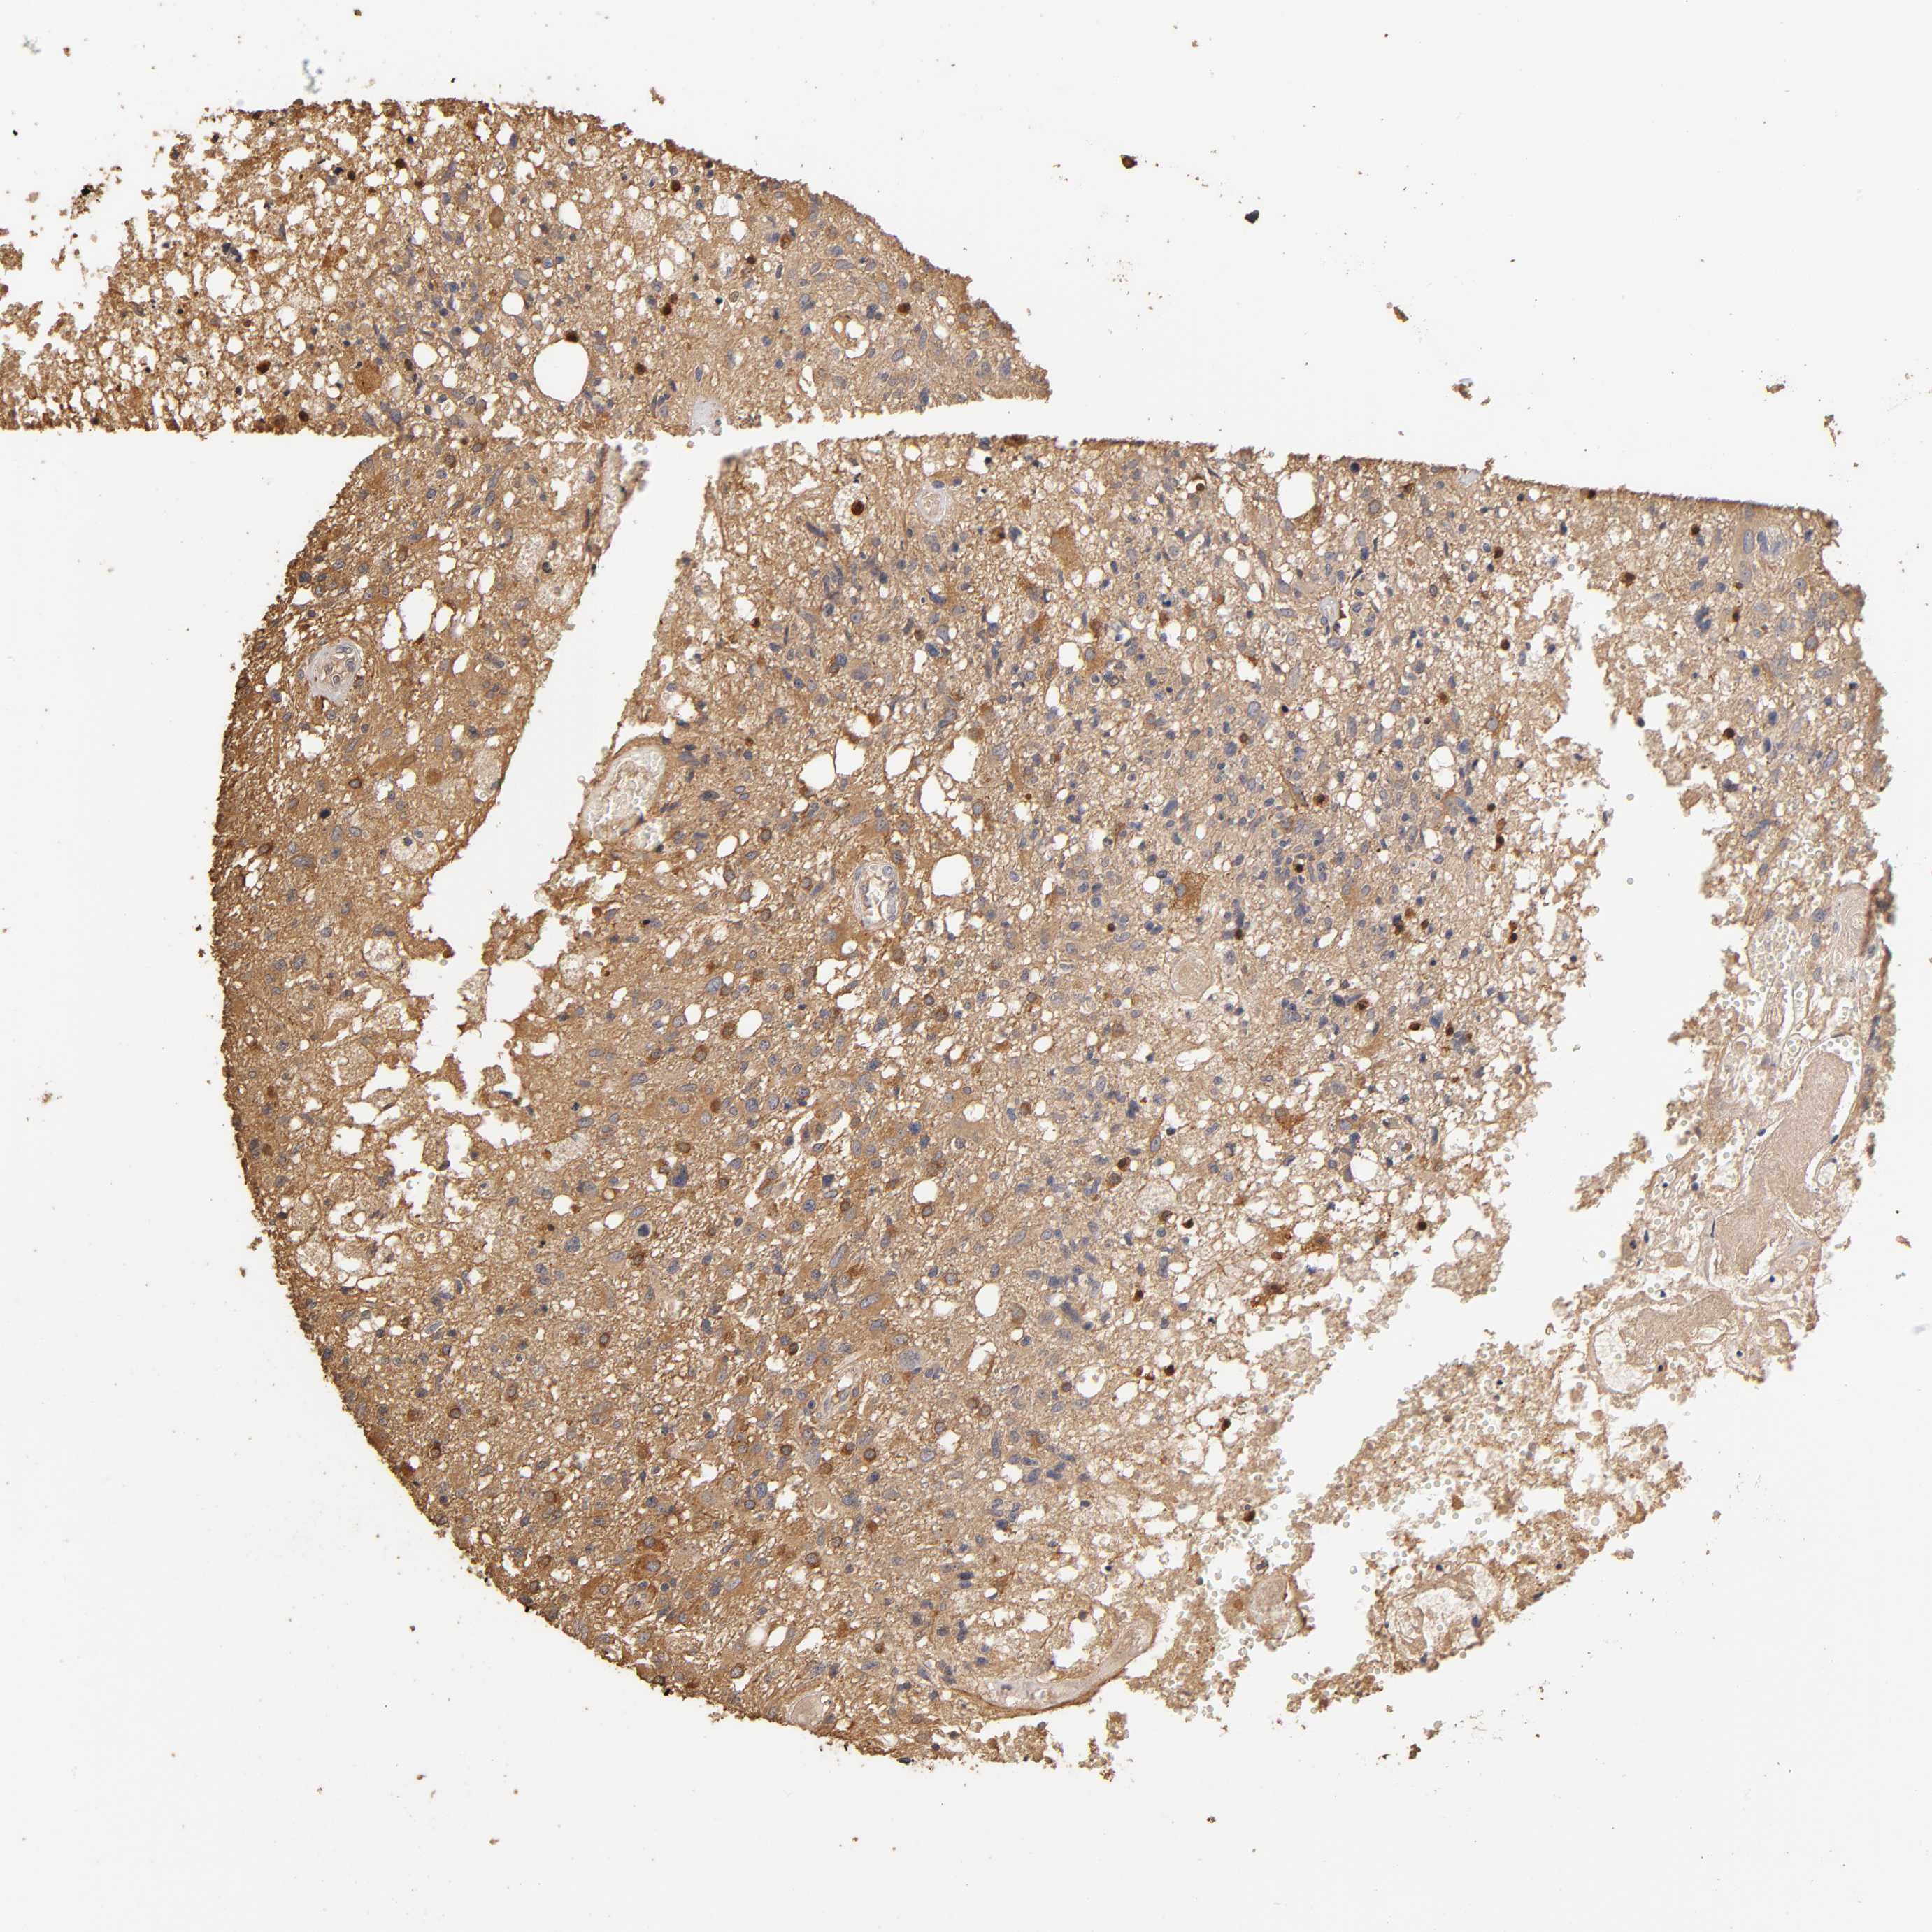

GLIOMA - Protein expressioni

A mouse-over function shows sample information and annotation data. Click on an image to view it in a full screen mode. Samples can be filtered based on level of antibody staining by selecting one or several of the following categories: high, medium, low and not detected. The assay and annotation is described here.

Note that samples used for immunohistochemistry by the Human Protein Atlas do not correspond to samples in the TCGA dataset.

Antibody stainingi

Antibody staining in the annotated cell types in the current human tissue is reported as not detected, low, medium, or high, based on conventional immunohistochemistry profiling in selected tissues. This score is based on the combination of the staining intensity and fraction of stained cells.

Each image is clickable and will lead to virtual microscopy that enables deeper exploration of all samples and also displays staining intensity scores, fraction scores and subcellular localization as well as patient and tissue information for each sample.

Antibody HPA003903

Antibody HPA072756

Antibody CAB026000

Staining

High

Medium

Low

Not detected

Intensity

Strong

Moderate

Weak

Negative

Quantity

>75%

75%-25%

<25%

None

Location

Nuclear

Cytoplasmic/membranous

Cytoplasmic/membranous,nuclear

Glioma, malignant, High grade

Glioma, malignant, NOS

Glioma, malignant, Low grade